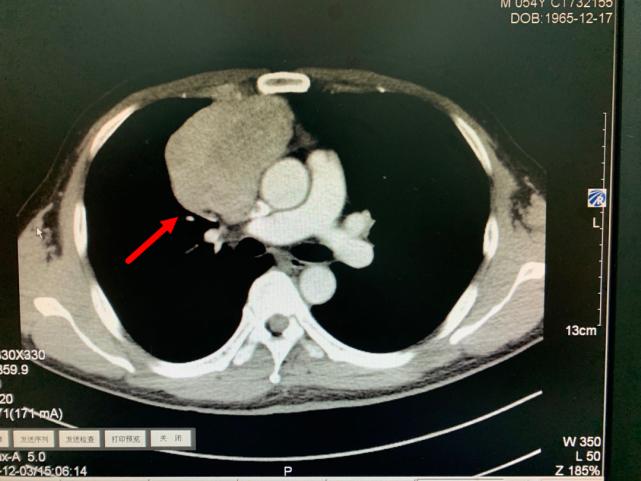

今年11月份,老方因“肠炎”在浙江省立同德医院肛肠科住院。“新冠”期间住院需要常规做胸部CT筛查,检查出来的结果却让他和医生们大吃一惊,胸部CT显示:胸腔内存在一个巨大肿瘤即纵膈肿瘤,大小约10.0cm×6.5cm×7.0cm,大小和一个成人男性拳头差不多。肿瘤紧靠着肺部、心脏及大血管,且与部分大血管有粘连,对重要的脏器已经造成了挤压。在确定胃肠道没有严重病患后,老方被转入心胸外科进一步作检查、治疗。

箭头所指为巨大纵隔肿瘤

肿瘤与周围血管存在黏连

叶中瑞主任医师通过进一步增强CT检查发现,老方体内的肿瘤巨大、与相邻的重要脏器粘连,界限不清,手术难度较大,且微创手术不适合,于是采取正中劈开胸骨的手术方式。手术过程顺利,术后恢复良好。第二天即下床活动。术后病理结果显示:纵膈肿瘤性质为中度恶性的胸腺肿瘤,后续还需要做进一步的放射治疗,以防止复发。老方在庆辛之余,他告诉叶中瑞主任医师,自己从今年开始每年都按时做体检,争取做到疾病早发现、早治疗,避免错过疾病的最佳治疗时机。